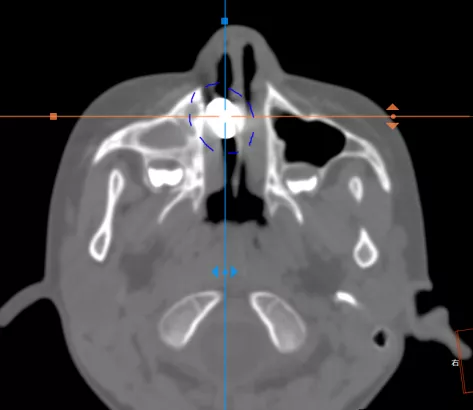

5歲男孩趁家長不注意,故意把一枚小零件往鼻孔裡塞,結果不小心猛的一吸,導致零件被吸到了鼻腔深處,怎麼也擤不出來,只有手術取出。